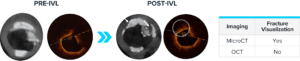

AVERAGE OF 3.2 FRACTURES PER LESION DEMONSTRATED BY OCT